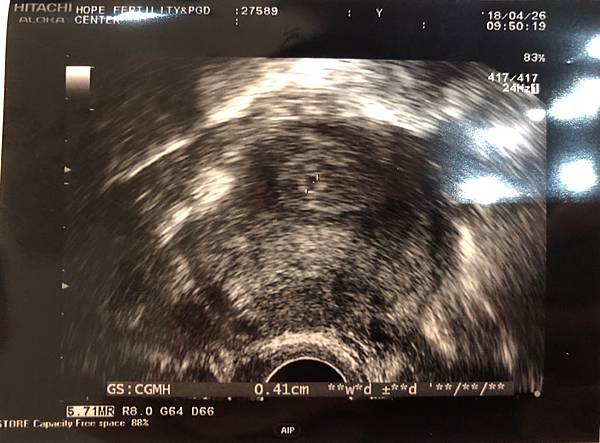

從植入到現在,R都因為出差所以不在身邊,真的很會挑時間,一出差就是2個月。今天我還是一個人到達診所。櫃檯的姊姊都已經可以記得進入療程的每位媽媽,其實要記那麼多的名字也真的很厲害。一到就是慣例的上廁所照超音波,在還沒揭曉答案前,我已經告知超音波技術員我的煩惱,一直很擔心子宮外孕。但是!!!!!今天,超音波一掃,沒有花多少時間,就有一個小小的胚囊乖乖的躺在子宮中間,喔天啊,我馬上說:『真的好險不是子宮外孕』。很像做了一個禮拜的雲霄飛車般,安全到達。

照完超音波進入陳醫師的診間,他還是依舊淡定,依舊少話。陳醫師說:『一開始成長得的比較慢,我們再繼續觀察,繼續吃藥。』

終於!!!!!過了第一關了。雖然成長速度慢,但有在成長和沒有出血都是好事。雖然諮詢師說,3個月前其實都是危險期,有很多無法推測的事情會發生。胚囊再來就是要有胚胎,然後有心跳,要一關一關的過才可以畢業。希望肚子裡的小胚囊,能夠乖乖的長大,能夠在6~8週照到心跳。